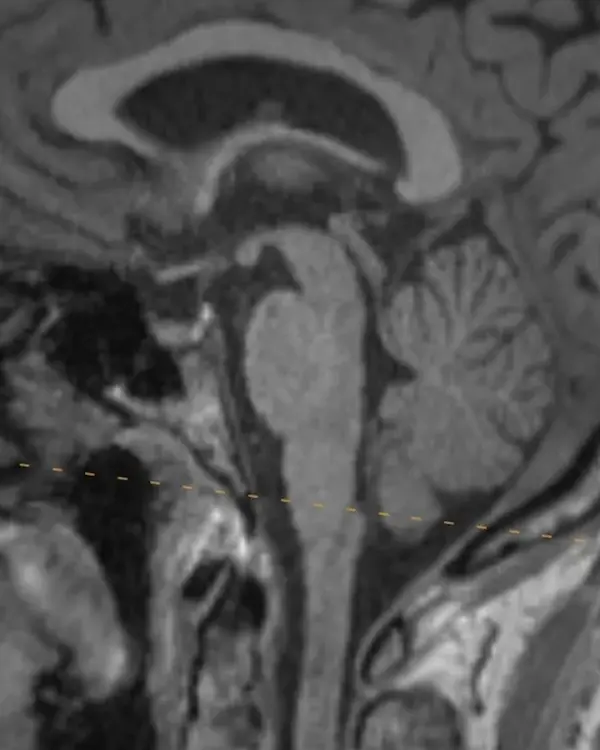

The brainstem, outlined in a white dotted line, is divided into the midbrain, pons, and medulla. Each segment has a characteristic appearance that is easiest to recognize in the sagittal plane.

Notice the beak-shaped anterior margin of the midbrain and the cerebrospinal fluid (CSF) space underneath it.

The pons has a bulbous contour anteriorly and a triangular shaped CSF space posterior to it.

The medulla is thin, gradually blends in appearance with the cervical spinal cord, and has a small CSF channel posterior to it.

Although easiest to see in the sagittal plane, these and some additional features that are unique to each division can be used to orient yourself in the axial plane.